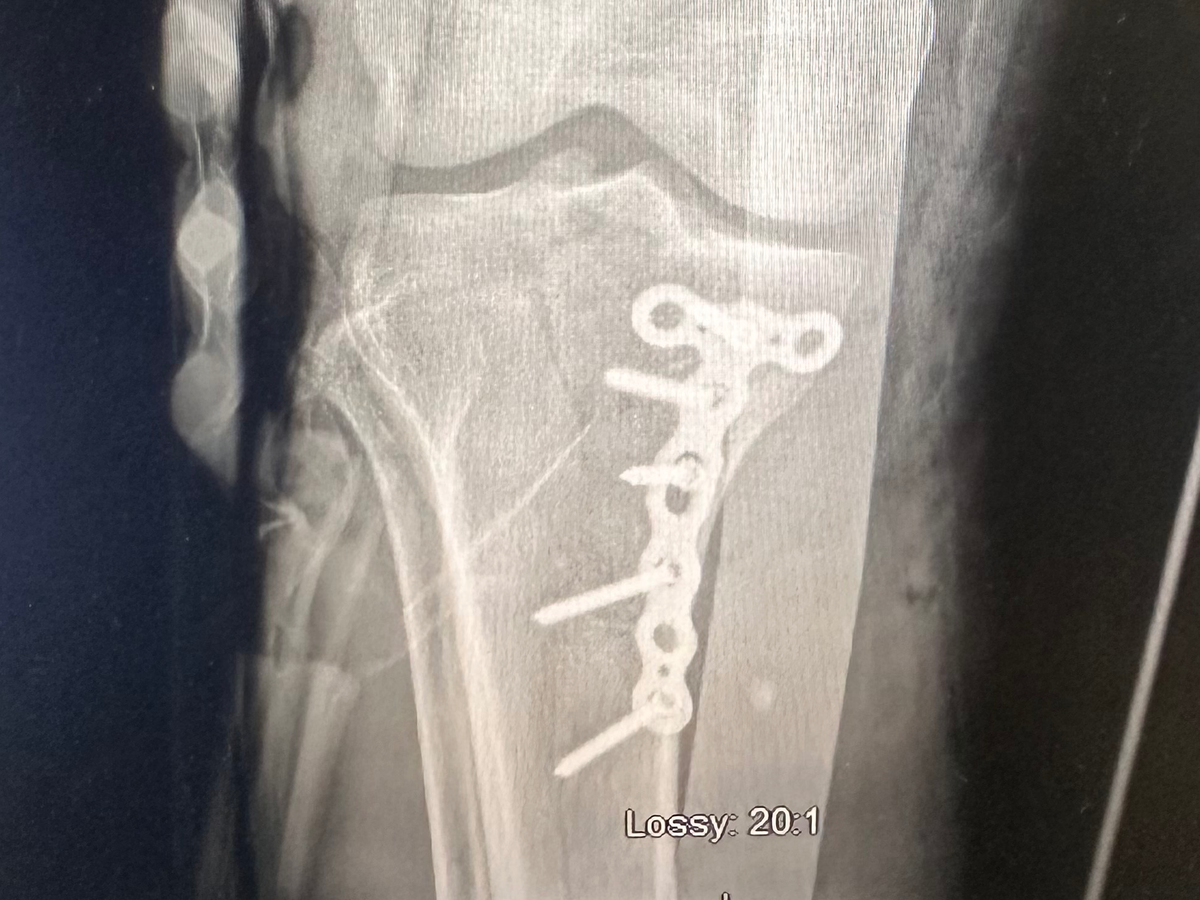

Hello, my name is Dream Smith, and I need urgent help to walk again. Four months ago, I suffered a traumatic leg injury that completely changed my life. I fractured my tibia and tore my ACL - both requiring surgery. I had my first surgery to repair the fracture with permanent rods and screws. But I was told immediately that I would also need ACL reconstructive surgery, or else I could become permanently disabled.